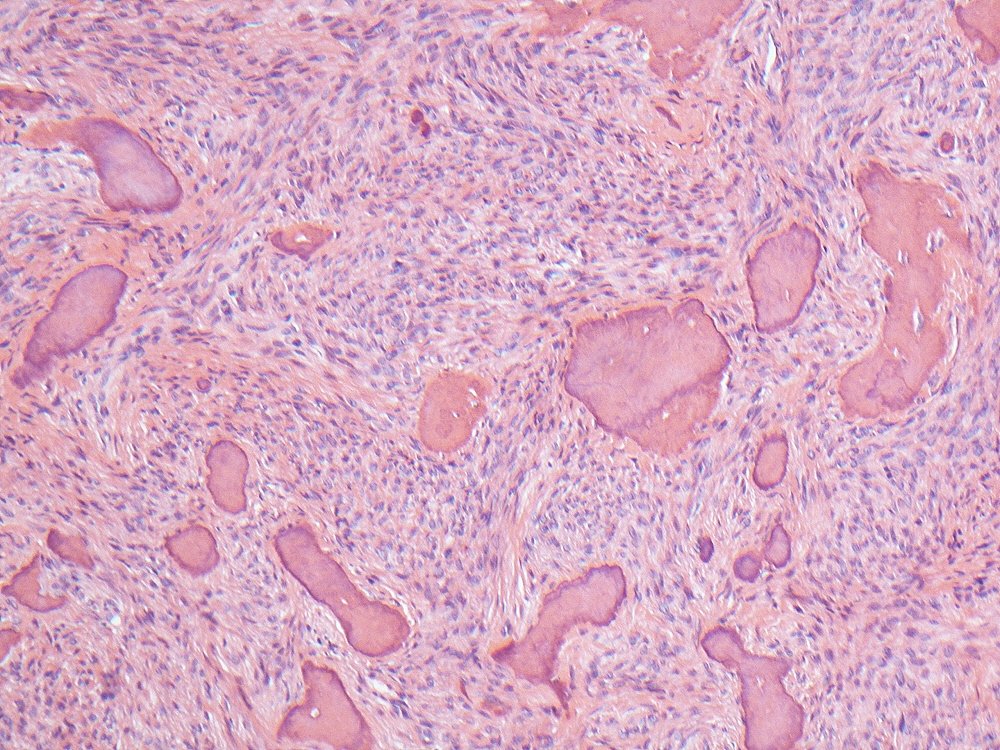

Section of a cemento-ossifying fibroma of the mandible. You won't find this under fibro-osseous lesions in the latest WHO classification; instead it's been grouped under 'benign mesenchymal odontogenic tumours' #oralpath #pathology #odontogenic